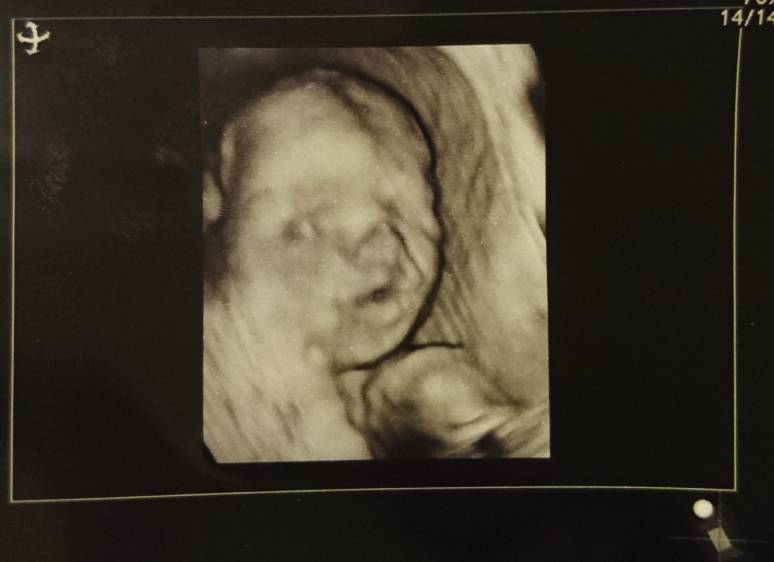

@Zinc ale cudnie i jak blisko buzię złapał. Mojego ciężko było złapać przez łożysko i naprawdę musiał się mój lekarz napracować by zrobić jakie kolwiek ujęcie.

@gie_er oo również suepr zdjęcie! mój również pośladkowo ułożony. Ale tym się przejmować nie trzeba, moja córka przekręcila się tydzień przed porodem dokładnie 41 tyg